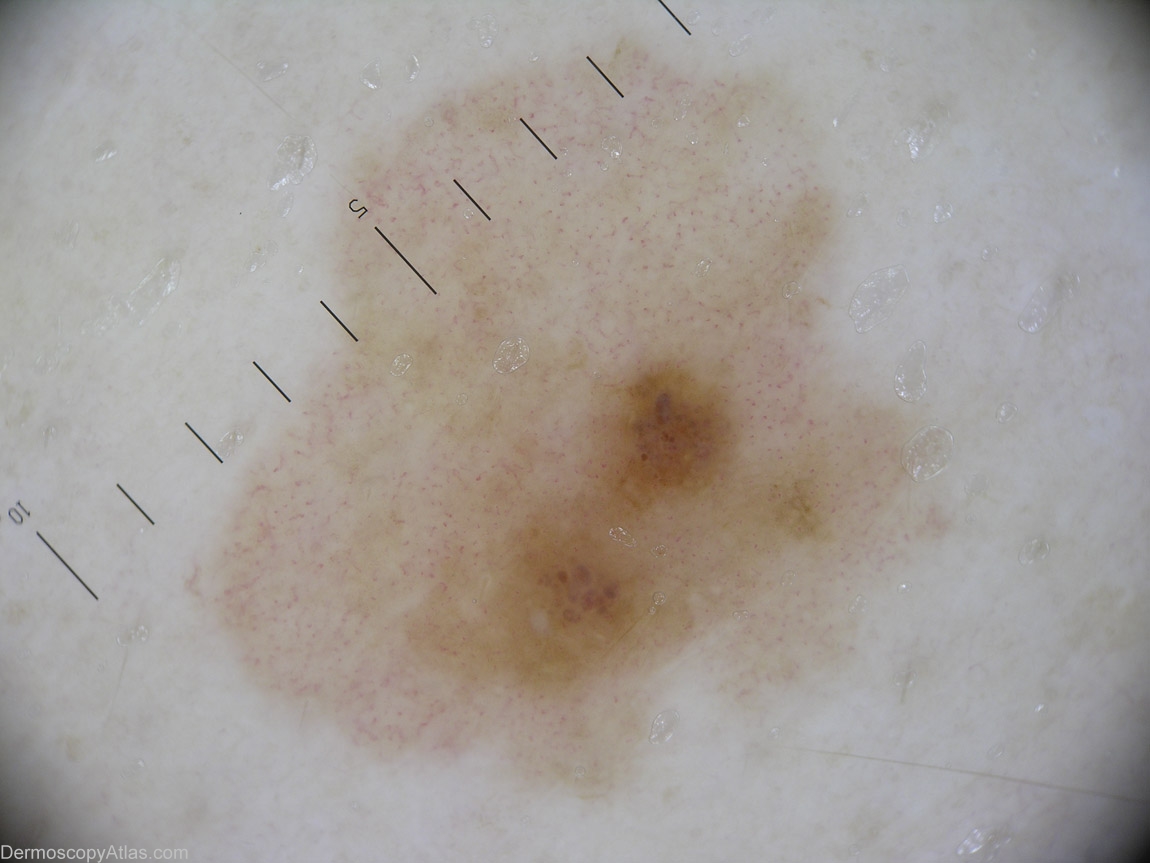

Diagnosis - Melanoma amelanotic

Diagnosis: Melanoma amelanotic